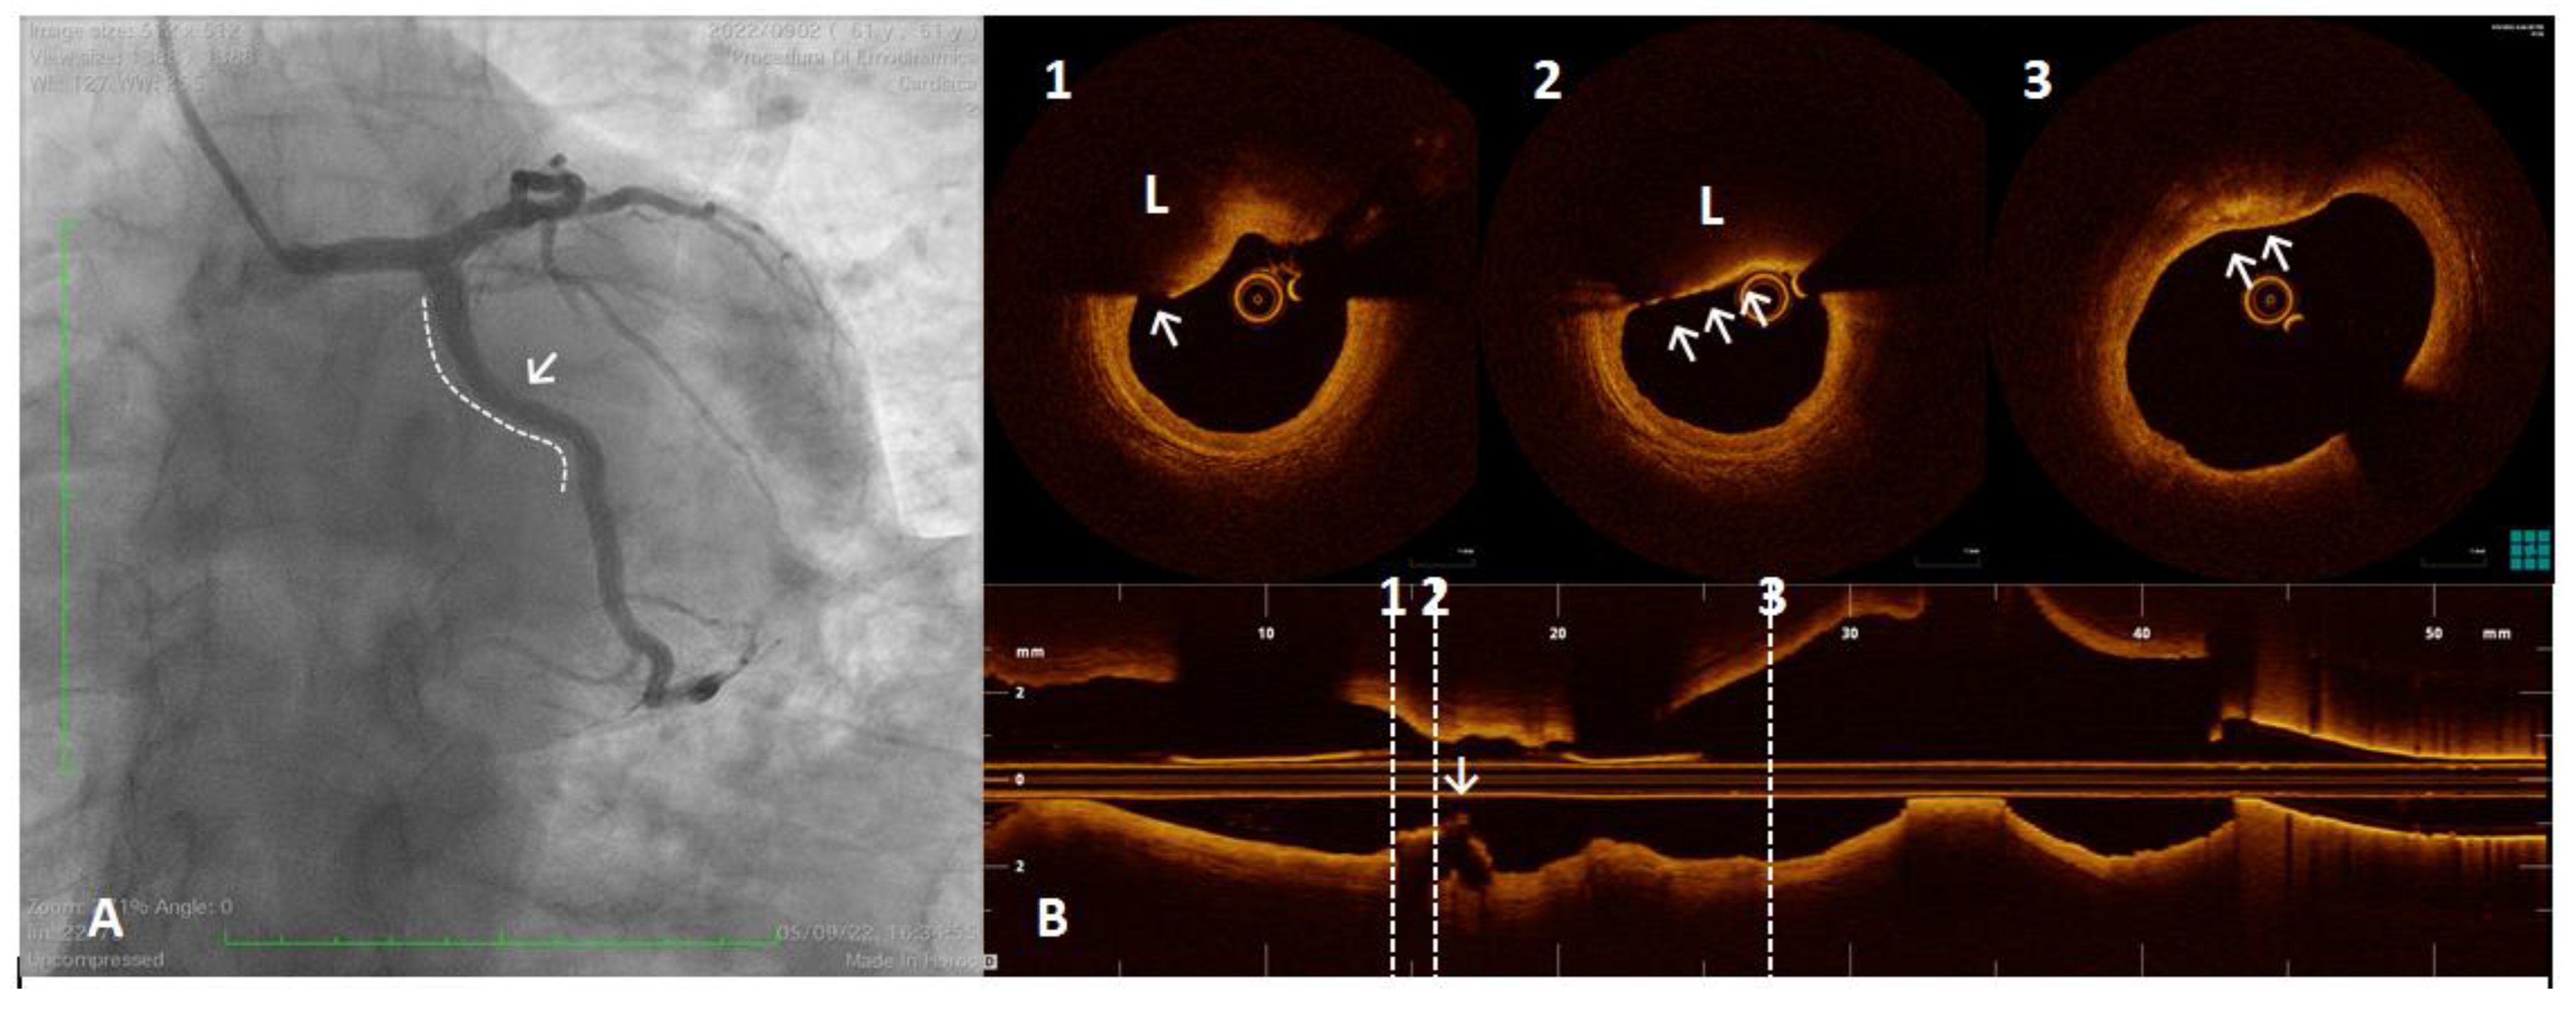

Figure 5.

A 61 year old man referred for Non-ST-segment elevation myocardial infarction (NSTEMI). Coronary angiography showed no significant coronary lesions. Left circumflex showed haziness at the proximal segment (panel (A), white arrow). The OCT pull-back showed a fractured plaque (panel (B), 1, white arrow) associated with a lipid pool (panel (B), 1 and 2, “L”); thin-cap fibro-atheroma and active macrophages are easily detected because of their typical bright line (2, white arrows) or spot images, within a fibro-lipidic plaque (3, white arrows).